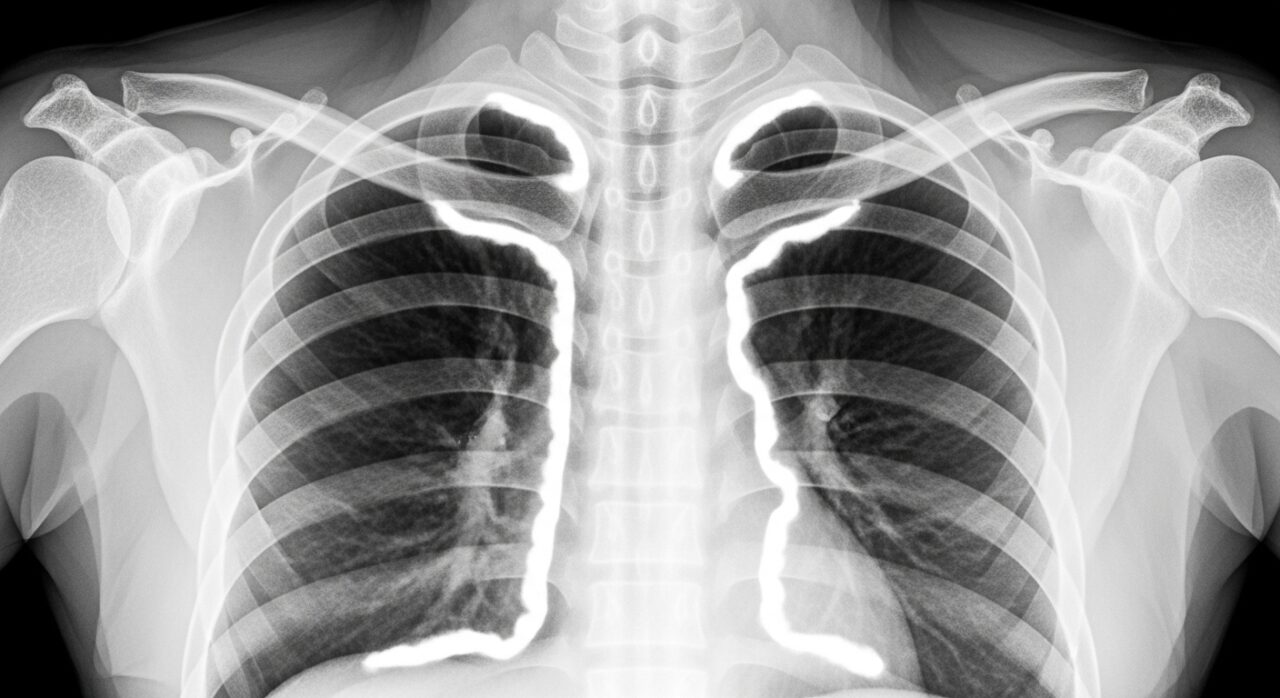

中皮腫を診断するための主な検査(画像診断・生検など)

中皮腫の診断は、X線検査やCTスキャン、MRIなどの画像診断で胸水や胸膜の肥厚を確認することから始まります。次に、確定診断のために最も重要なのが「生検」です。胸水の一部や、胸膜組織を採取して顕微鏡で調べる病理検査により、中皮腫細胞の有無や種類(上皮様型、肉腫様型、二相型)を特定します。正確な診断が、その後の適切な中皮腫治療方針を決定する上で極めて重要になります。